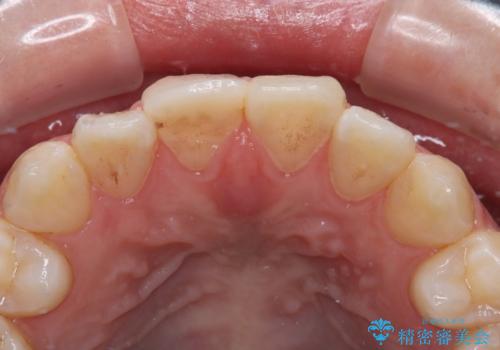

- 前歯が欠けてしまい、保険診療の樹脂の材料で修復していた前歯をきれいにしたいと来院された患者様です。

歯の約半分が欠けてしまっているため、樹脂の材料での修復には限界があります。

土台の形を整えて、精度の高いシリコーンによる型どりを行いました。